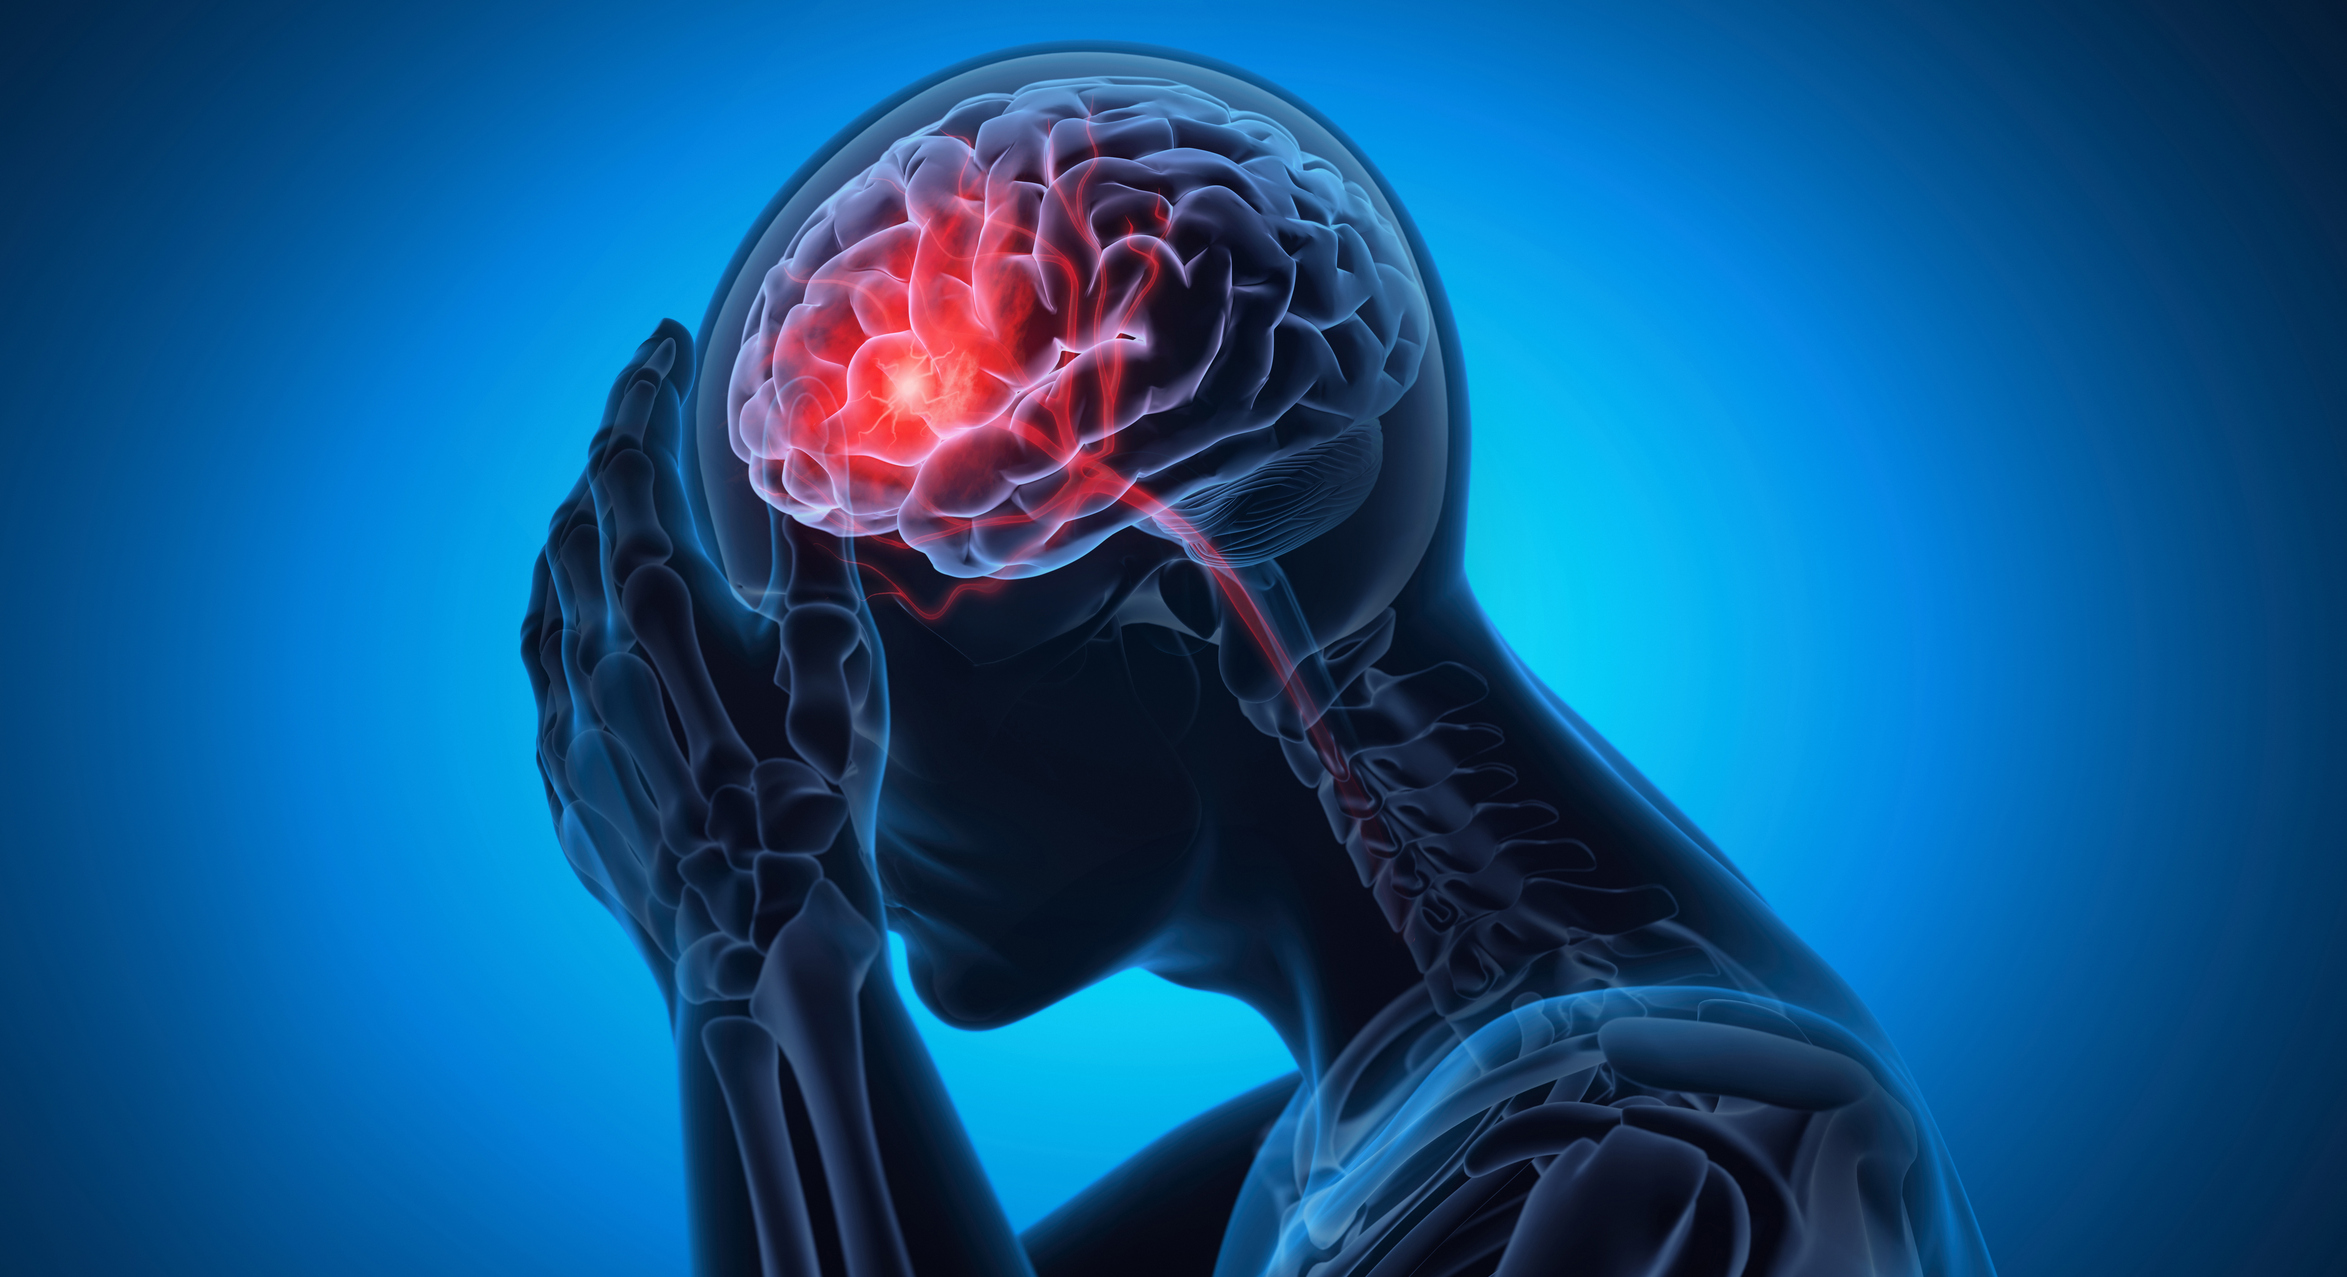

Generalmente, al pensar en medicina, podríamos imaginar un dolor alojado en un lugar específico de una persona...